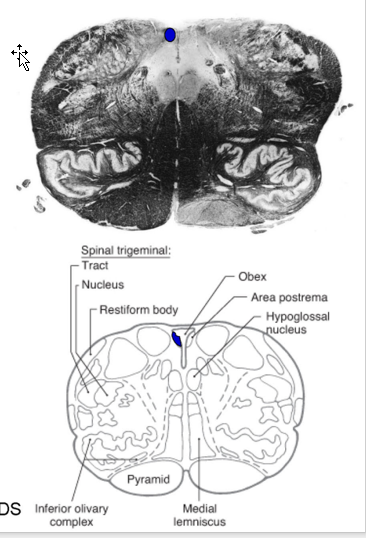

Describe the Upper Medulla:

What is it?

Boundaries?

Describe Development:

Where are Sensory/Motor CN nuclei?

Movement of SVE/GSA column

What forms the inferior Olive?

Level of Obex:

associated w/?

Decussation Characteristics?

What is a unique Characteristic @ this level? Function?

Open portion of medulla containing caudal half of the fourth ventricle.

Boundaries:

Dorsal Surface:

caudal boundary= obex

rostral boundary is the striae medullares

Ventral Surface:

no definitive caudal boundary

rostral boundary = inferior pontine sulcus

Development:

sensory CN nuclei: dorsolateral position due to dev. of 4th ventricle.

Motor CN nuclei: ventromedially.

SVE/GSA column will migrate anterolaterally.

inferior olive = alar plate derivative.

Associated w/ CN XII

Many of characteristics of level of the sensory decussation are retained.

Unique characteristics: Area Postrema

Circumventrical organ containing sinusoid capillaries

Function:

Chemosensitive trigger zone for emesis stimulated by blood-borne chemicals